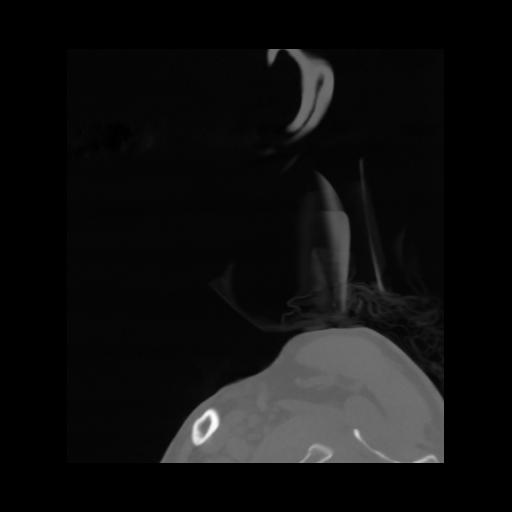

14 P.BLANDAS,,Sagittal,2.000,P.BLANDAS,Sagittal,